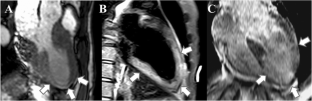

Fig. 1